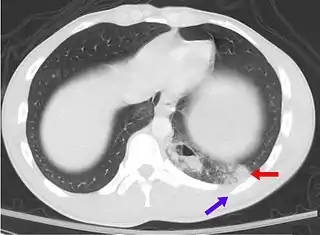

Contusión pulmonar (flecha roja) por fractura de costilla.